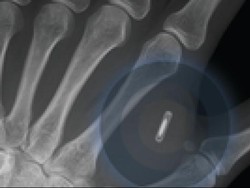

Amal Graffstra, memasang 2 microchip ke tangan dan pergelangannya, memungkinkannya membuka komputer dan rumah miliknya dengan gelombang sederhana.